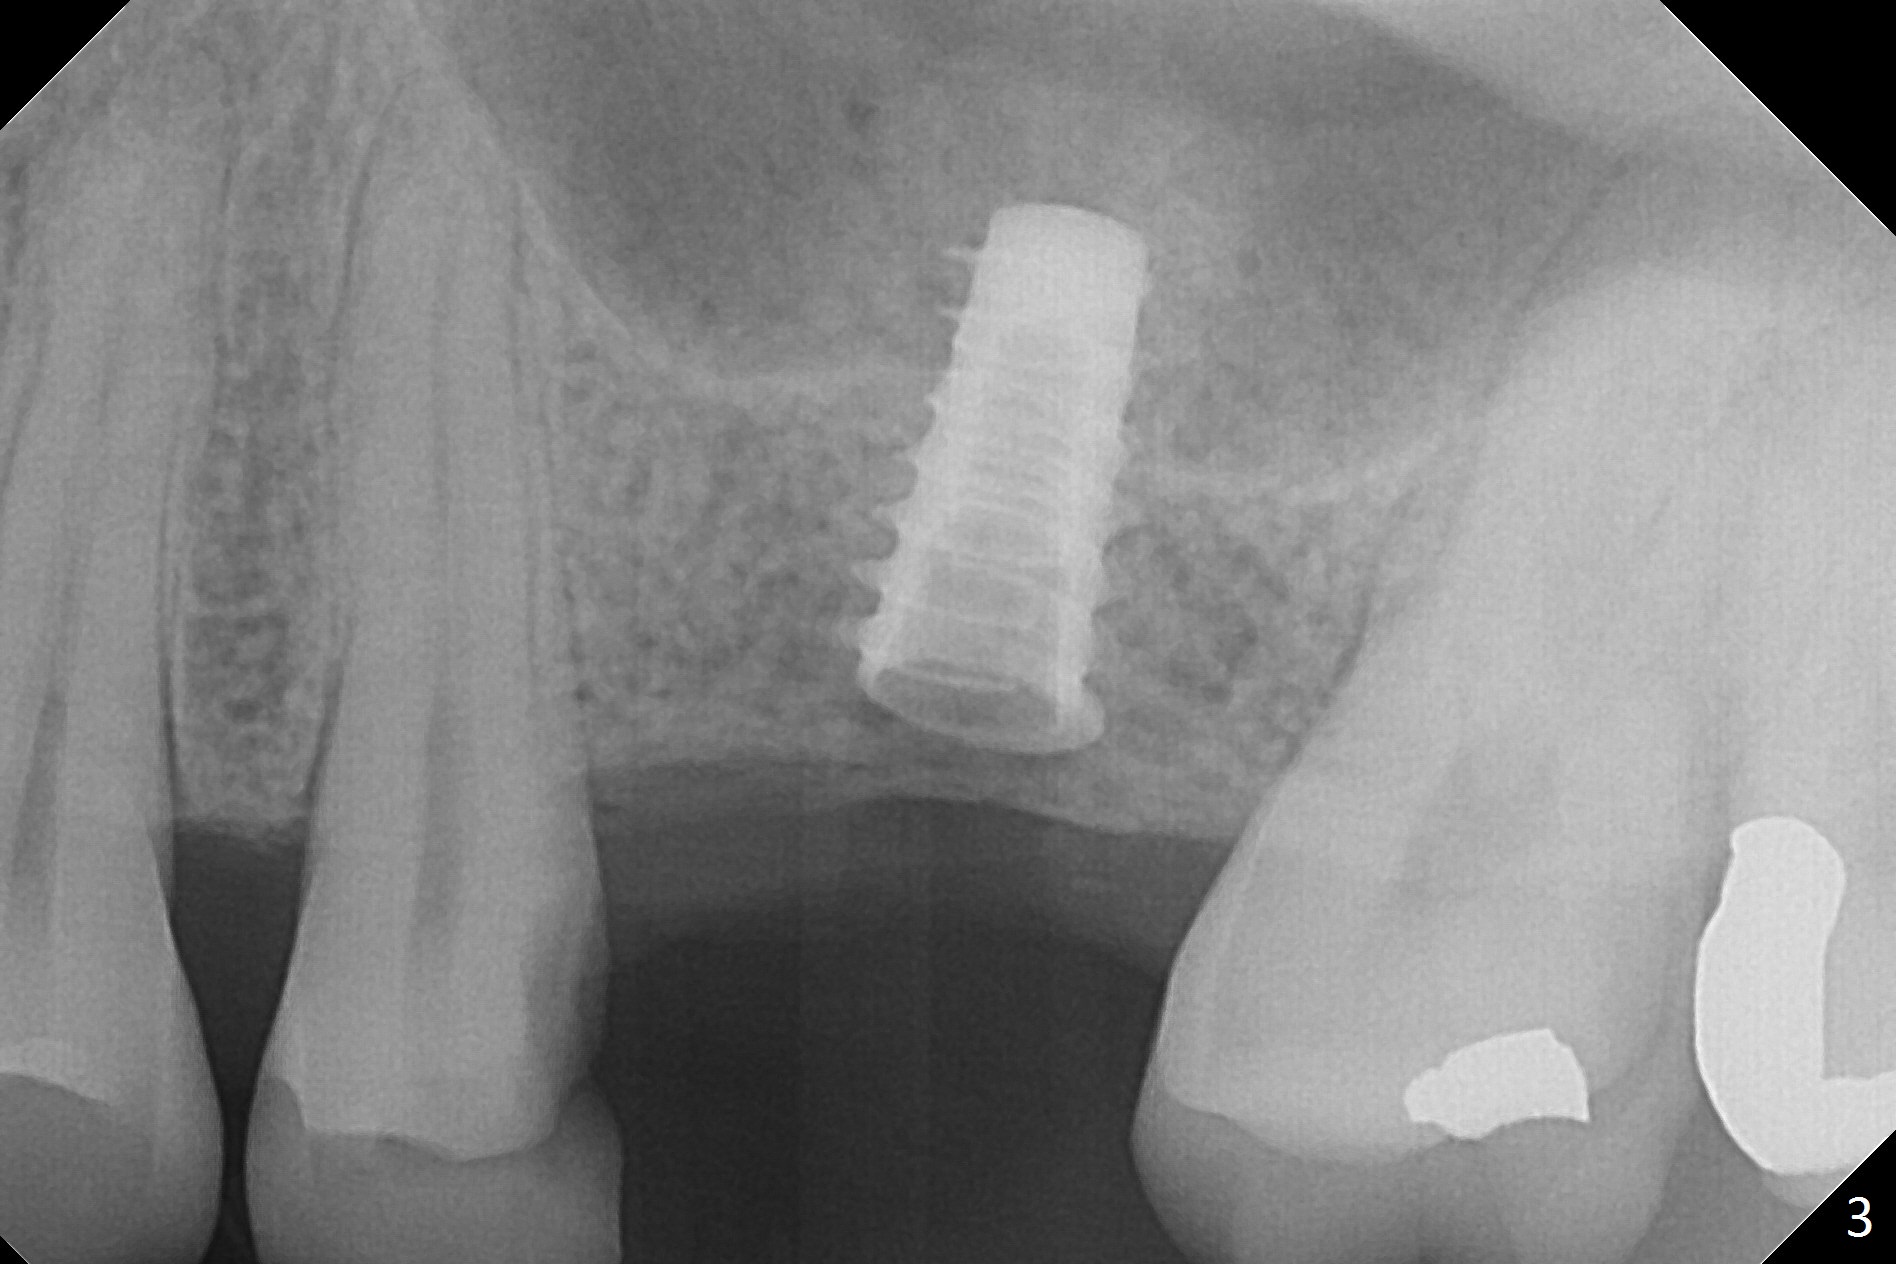

While the base of the ridge at #14 is wide, the top is moderate. IBS Magic Split is applied to gain access and test bone density (flapless). In fact the bone is hard. A 1.6 mm pilot drill is used for 9 mm (gingival level), followed by insertion of a parallel pin (Fig.1). Following Magic Expander 3.0 mm and Magic Drill 3.8 mm for ~ 11 mm (with empty feeling without air leak), a 4x11 mm dummy implant is placed with 25 Ncm (Fig.2). After insertion of a 4.5x11 mm dummy implant at 9 mm (35 Ncm; for further bone expansion), one piece of PRF plug and 1 piece of PRF membrane are pushed into the osteotomy, followed by allograft mixed with autogenous bone for sinus lift and placement of a 5x9 mm implant (Fig.3,4 with insertion torque >50 Ncm). A 6x4(2) mm abutment is placed for fabrication of an immediate provisional (Fig.5 P). There is no nasal hemorrhage postop. PRF membrane and plug are used to prevent and repair sinus membrane perforation and facilitate wound healing. There is mild bone resorption at the crest 11 months postop (Fig.6,7). The bone resorption seems to be worse 8 months post cementation (Fig.8,9); in fact the abutment screw is loose.